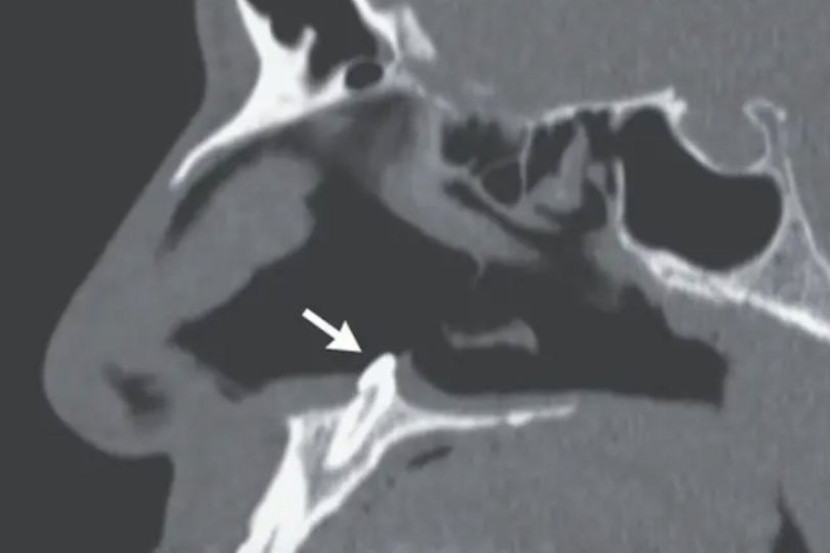

Susulan masalah pernafasan, lelaki berusia 38 tahun itu berkunjung ke sebuah klinik dan pemeriksaan awal mendapati dia diagnosis mempunyai septum yang menyimpang dan taji septum yang berkalsifikasi.

Doktor melakukan rhinoskopi, prosedur untuk memeriksa hidung dan mendapati objek putih tumbuh di dalam hidungnya.

Ia dikenal pasti sebagai gigi ektopik di mana sememangnya tumbuh di dalam hidung.

Gigi tumbuh di dalam hidung. fotoThe New England Journal of Medicine

Menerusi The New England Journal of Medicine, Sagar Khanna dan Michael Turner menulis: "Pemeriksaan fizikal hidung menunjukkan sisihan septum, taji septum berkalsifikasi, dan perforasi dua sentimeter pada septum posterior."

"Gigi itu telah dikeluarkan menerusi pembedahan oral dan otolaryngologic melalui pendekatan intranasal. Ia berukuran 14 milimeter (mm) panjang.